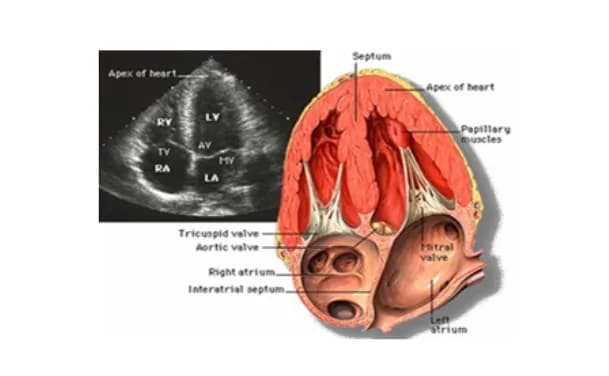

Các kiểu siêu âm tim

Siêu âm tim: Các kiểu siêu âm thường dùng

Siêu âm tim là một kỹ thuật chẩn đoán hình ảnh không xâm lấn, sử dụng sóng siê...